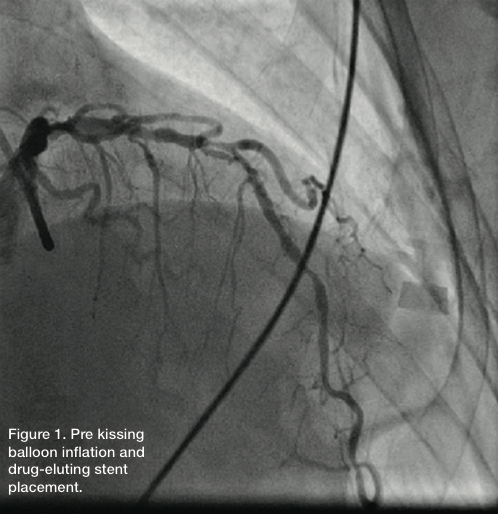

At this point, we were able to easily advance the 2.5 x

15mm AngioSculpt balloon. The LAD was predilated, with no significant compromise of the diagonal at this point. Following predilatation, a 2.75 x 20 Promus drug-eluting stent (Boston Scientific) was advanced and the buddy wire removed. The stent was deployed at 12 atm, followed by another inflation at 12 atm. The LAD had good flow, with an excellent angiographic result. However, there was compromise of the diagonal, which had no significant angiographic stenosis in the beginning, but 99% ostial disease.